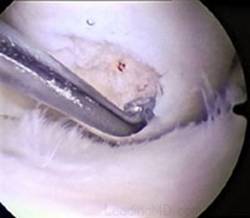

Chirurgul trebuie sa fie foarte atent atunci cand examineaza posteriorul condililor femurali. Daca se semnaleaza orice vatamare/rana/deteriorare pe suprafetele articulare, trebuie sa se cerceteze atent calitatea cartilagiului. Orice flapsuri instabile sunt inlaturate prin folosirea unui aparat de ras electric artroscopic sau curette. Apoi, un curette este folosit pentru a debrida stratul de cartilagiu calcifiat de la baza in toata grosimea defectului. Acest pas se bazeaza pe activitatea lui Frisbi, care a demonstrat vindecarea suprafetei articulare superioare la un cal, cand stratul cartilagiului calcifiat este indepartat. Cand indepartam stratul cartilagiului calcifiat, in general nu se foloseste un aparat de ras. Cu un aparat de ras este dificil de controlat cantitatea de os eliminat, si este posibil ca osul subcondral sa fie afectat.

Dupa indepartarea cu succes a stratului de cartilaj calcifiat, o andrea este folosita pentru a face mai multe gauri mici (mirofracturi) in osul expus al defectului condral aflate la distanta de 1-2 mm. Trebuie lasata o punte de oase potrivita intre gauri. Tehnica de microfracturi are numeroase avantaje fata de foraj. Mai intai de toate, creaza o leziune termala mai mica. Mai mult, cu microfracturi, chirurgul este capabil sa intre in zonele dificile ale suprafetei articulare cu un control mai bun asupra adancimii de patrundere. La finalizarea microfracturii, o suprafata aspra este generata pentru a aderenta cheagului de sange care contine celule mezenchimale nediferentiate de la osul subcondral. Trebuie avut grija ca cele mai marginase parti ale leziuni sa fie patrunse de andrea pentru a ajuta la vindecarea tesutului reparator la imprejmuirea suprafetei articulare. Odata ce microfractura este finalizata, pompa artroscopica este oprita pentru a se asigura ca sangerarea maduvei curge din gaurile mici umpland defectul.[54]

Fig.25.a. Debridarea. Fig.25.b. Microfracturare.